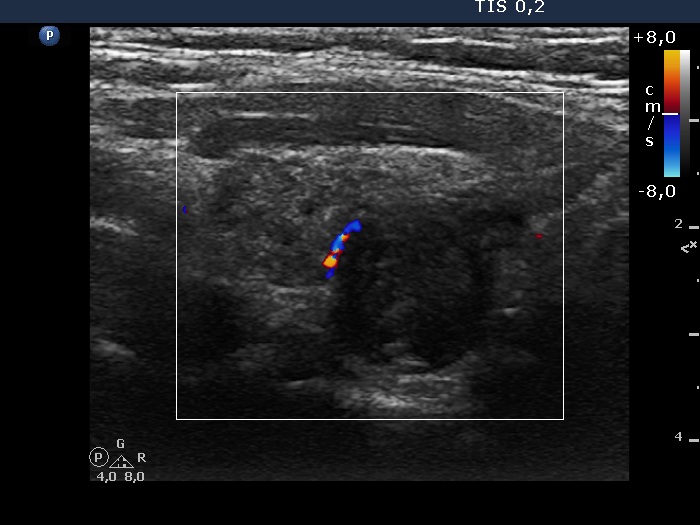

Two years after the initial examination (ultrasonographic picture 5)

Right lobe, longitudinal view, color Doppler mode. The nodule shows signs of perinodular vascularity.